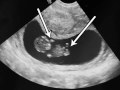

فحص الموجات فوق الصوتية في الأسبوع العاشر من الحمل شورتات

سونار الحمل في الأسبوع العاشر و توأم أيضا

منظار رحمي لحامل بالاسبوع العاشر سبحان الله